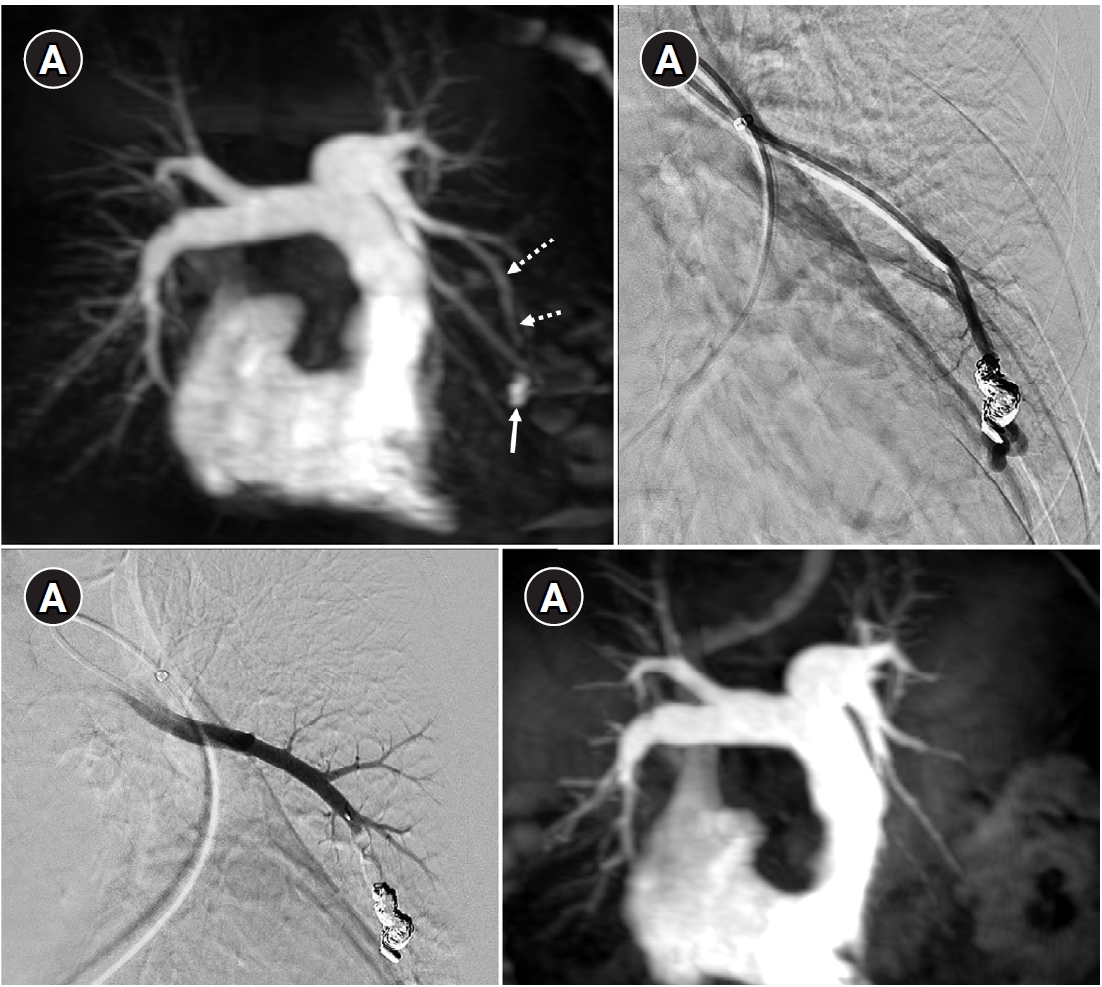

Fig. 5.

Embolization procedure in a patient with a feeding artery diameter of 2.6 mm and a venous sac diameter of 8 mm in the right lower lobe. (A) Selective angiography of the right lower lobe pulmonary arteriovenous malformation. (B) A 7 mm Amplatzer vascular plug type IV (arrow) was deployed into an approximately 8 mm venous sac, and it was determined that this would not provide adequate embolization effect. (C) By repositioning the Amplatzer plug and deploying it at the distal part of the feeding artery (arrow), it becomes clear that an Amplatzer vascular plug sufficiently larger than the feeding artery’s size is needed to effectively achieve embolization.

Historically, detachable balloons were used as an embolization material; however, they are no longer utilized in current practice [18]. In the context of PAVM embolization, the use of coils, vascular plugs, or a combination of both is now standard practice [19-21]. Since the development of detachable coils, they have offered advantages over pushable coils, particularly in terms of repositioning during the procedure. They can even be fully retrieved and redeployed if necessary, enhancing procedural safety and control. It is crucial to prioritize minimizing the recanalization rate while ensuring the overall safety of the procedure when selecting the appropriate embolic materials and techniques. Feeding artery coil embolization was historically regarded as the standard approach, whereas venous sac embolization was discouraged because of the perceived risk of rupture [22]. However, with the introduction of newer venous sac embolization techniques, recent findings now indicate that tightly packing the venous sac with coils can achieve a higher success rate than the traditional feeding artery approach (Fig. 2) [22-25]. Additionally, vascular plugs, including micro-vascular plugs (Medtronic, Minneapolis, MN, USA) and Amplatzer vascular plugs (Abbott Vascular, Saint Paul, MN, USA) have also demonstrated a higher success rate compared to feeding artery coil embolization (Fig. 4) [26-28]. In the case of vascular plugs, the risk of device migration is relatively low. Moreover, an additional advantage is that the device can be repositioned if the sizing is not ideal or if it is not deployed in the exact desired location. This flexibility enhances the precision of the procedure (Fig. 5). In a recent European guideline, there is also a recommendation to consider vascular plug embolization as a first-line option whenever possible, rather than coil embolization [11]. Additionally, a recent meta-analysis recommended vascular plugs or venous sac coil embolization, noting that vascular plugs had a recanalization rate of 13.6% compared to 32.7% for coil-only embolization. Similarly, venous sac embolization showed a 3.8% recanalization rate, while feeding artery embolization had a rate of 24.3%. Additionally, a recent meta-analysis has recommended the use of vascular plug or venous sac coil embolization, as these techniques have demonstrated a lower persistence rate compared to other methods [21]. This shift is largely in response to the relatively high recanalization rate associated with feeding coil embolization. In the case of embolization using vascular plugs, the plug should be deployed at the most distal segment of the feeding artery just before the venous sac in order to preserve the normal pulmonary artery. Since the pulmonary artery contains less elastin and has a thinner wall compared to systemic arteries, it is more distensible [29]. Therefore, in the author's experience, oversizing by about 50% to 100% has been effective in reducing the recanalization rate. When performing venous sac coil embolization, it is important to use coils large enough to create a stable framing coil larger than the draining vein diameter, thereby preventing coil migration. After establishing this frame, the venous sac and the proximal feeding artery should be carefully packed to achieve complete occlusion.